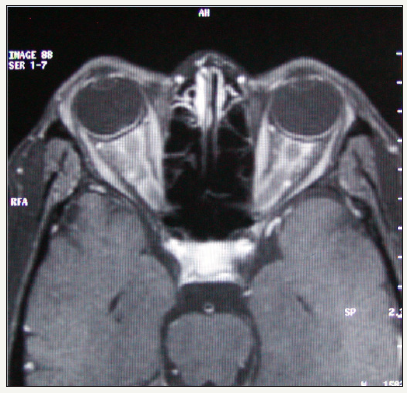

42 years old women, who has been diagnosed as NHL, was presented with bilateral, severe visual loss for two weeks, when she was under remission. Lumbar puncture, bone marrow examination and brain CT were all normal. On examination, visual acuity was no light perception in both eyes, both pupils were fixed and unresponsive to light. There was no extraocular motility disturbance. On fundus examination, ischemic whitening of the retina, increased venous tortuosity, cherry red spot appearance, scattered intraretinal and preretinal hemorrhages and swollen optic disc was detected in both eyes (Figure 1 & 2). Orbital CT and MRI showed thickening of both optic nerves, and perineural enhancement was seen following contrast administration (Figure 3). Then the patient was diagnosed as, bilateral combined central retinal artery and vein oclusion due to optic nerve tumoral involvement and treated with orbital radiotherapy. Visual acuity didn’t improve, and the patient was died 7 months after the optic nerve involvement.

Figure 3:MRI scan of case 1. Thickened optic nerves and contrast enhancement of perineural tissue, more prominent on right side.